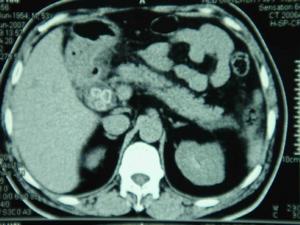

膽道6.CT檢查CT對了解膽道梗阻部位,與上述超聲檢查所見有同樣的診斷價值;CT在顯示膽囊病變或膽囊腫瘤、肝實質占位病變、肝門與後腹膜淋巴結有無受累及胰頭體尾病變等方面比超聲檢查更為清晰。磁共振膽胰管成像(MRCP)對診斷膽道梗阻極有幫助。